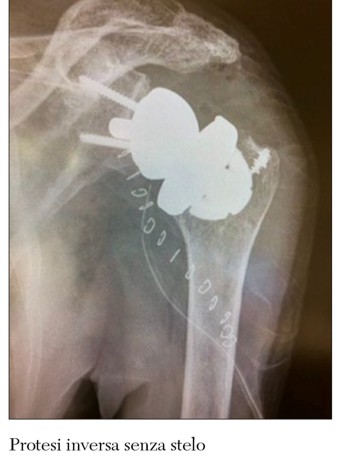

La protesi di spalla fu utilizzata diffusamente negli Stati Uniti a partire dal 1970, per la cura delle fratture a più frammenti dell’omero prossimale. Nel corso degli anni la tecnologia e l’innovazione hanno sviluppato impianti sempre più precisi nel ricreare l’anatomia articolare producendo protesi modulari adattabili a ogni paziente. Al momento sono disponibili protesi a risparmio di tessuto osseo ovvero protesi applicabili con minime resezioni ossee. Nel nostro Centro utilizziamo protesi di spalla senza stelo o con steli di lunghezza minima che consentono di ridurre l’invasività chirurgica e di riprodurre un’anatomia il più vicino possibile a quella normale promuovendo una ripresa funzionale più rapida.

La protesi totale inversa si utilizza per ripristinare il movimento della spalla nei pazienti affetti da un arto pseudo paralitico ovvero che sono incapaci di sollevare la mano sopra la testa in conseguenza della cronica insufficienza dei tendini della cuffia dei rotatori. La protesi è chiamata inversa perché applichiamo la cupola sulla glenoide scapolare, mentre la coppa viene inserita sull’omero.

Le protesi senza stelo hanno il vantaggio di adattarsi alla struttura anatomica del paziente anche nei casi di dismorfismo sia esso degenerativo che postfratturativo. Inoltre tale impianto riduce il rischio di gravi complicanze quali le fratture periprotesiche e l’instabilità articolare. Infine, l’utilizzo di questo tipo di protesi di spalla facilita l’eventuale intervento di revisione.

L’utilizzo delle protesi di spalla è sempre più diffuso con buoni risultati a breve e medio termine. La disponibilità di protesi senza stelo o con steli corti ha facilitato e implementato il loro utilizzo in quanto tali impianti sono più facili da applicare con un minore impegno chirurgico. Inoltre la letteratura mostra che i risultati delle protesi di spalla senza stelo sono sovrapponibili a quelli delle protesi tradizionali e che queste sono anche migliori dopo intervento di revisione protesica.